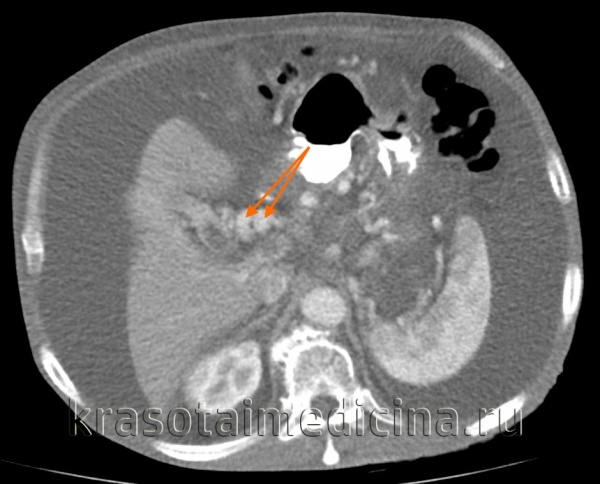

КТ ОБП. Портальная гипертензия на фоне обструкции воротной вены опухолью поджелудочной железы (красная стрелка). Опухолевый тромб (зеленая стрелка) в воротной вене. Асцит (белая стрелка).